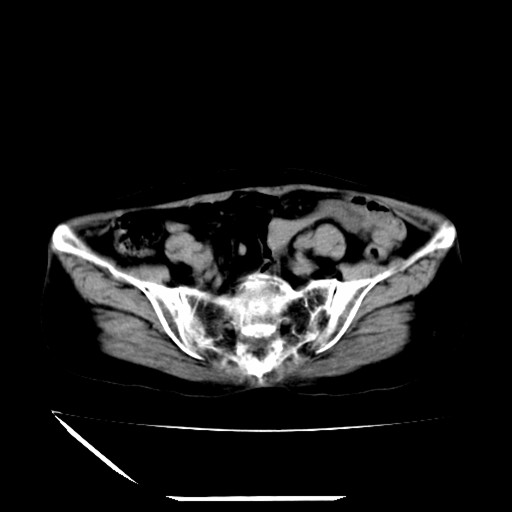

标题: CT16840:女-63岁,下腹部疼痛, [打印本页]

标题: CT16840:女-63岁,下腹部疼痛,

补充资料:血象是13.5,临床拟诊阑尾炎

盆腔少量积液   支持

道格拉斯窝内少量积液。

支持 阑尾炎,盆腔少量积液。